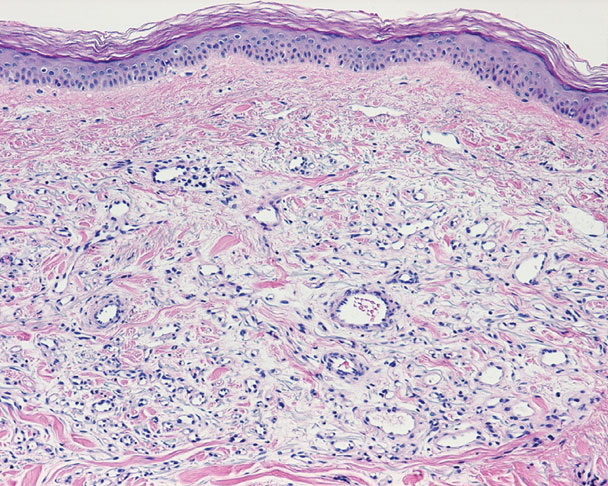

microvenular-hemangioma